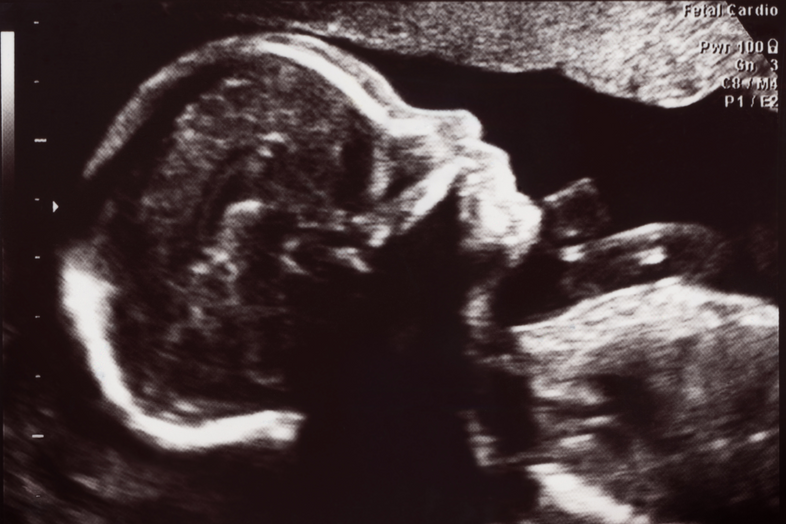

After 5 cycles, each with confirmed ovulation, baby #4 is on the way! It took more cycles this time than with my other 3, but knowing everything was balanced actually made the whole process less stressful. In fact, this has been the least stressful one for us because we knew everything was fine from the data and we could see the numbers and trends.